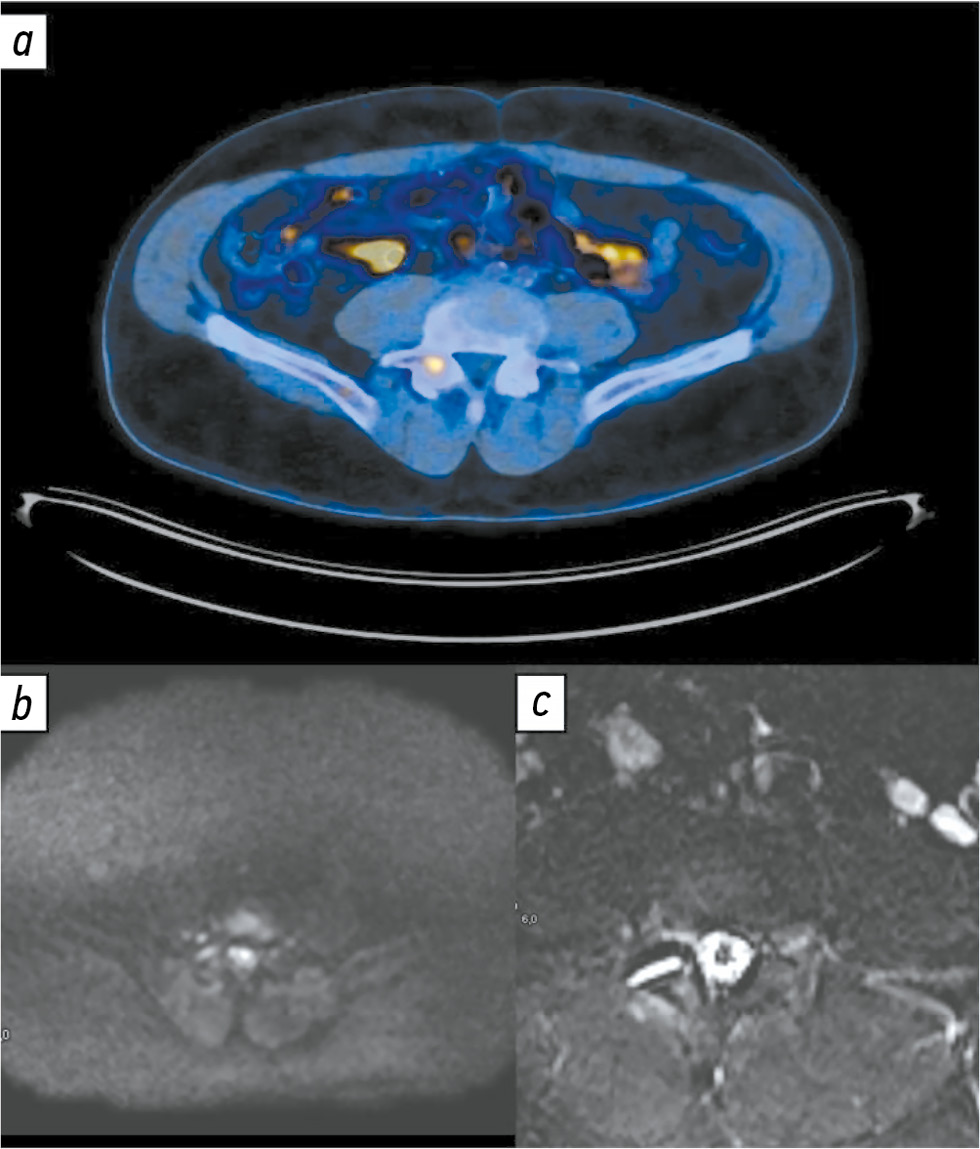

Серьёзной проблемой, с которой сталкивается врач-рентгенолог при интерпретации ДВИ костей, является ограничение диффузии в таких доброкачественных структурах, как очаги реконверсии красного костного мозга. Дифференциальная диагностика таких очагов возможна с использованием импульсных последовательностей с селективным жироподавлением (Т1-ВИ по методу Dixon) [26, 27]. Дегенеративные изменения позвоночника также нередко сопровождаются признаками ограничения диффузии (рис. 2). Применение импульсных последовательностей с селективным жироподавлением позволяет надёжно дифференцировать метастазы и узлы Шморля [28].

Рис. 2. Пациент Б 77 лет с аденокарциномой предстательной железы T4N2M0, Глисон 8 (4+4). Состояние после комплексного лечения, нескольких линий гормональной терапии, химиотерапии, лучевой терапии предстательной железы, зон регионарных лимфатических узлов. Повышение содержания общего простатоспецифичного антигена сыворотки крови до 0,4 нг/мл. Пример ложноположительного результата: а ― изображение позитронно-эмиссионной компьютерной томографии с 18F-простатоспецифичным мембранным антигеном-1007 в аксиальной плоскости: в правой дужке LV позвонка отмечен очаг гиперфиксации радиофармацевтического препарата, подозрительный в отношении метастатического процесса; b и с ― диффузионно-взвешенное (b) и Т2-взвешенное изображение магнитно-резонансной томографии (с): признаки артрита правого дугоотростчатого сочленения LV-SI в виде внутрисуставного выпота, умеренного трабекулярного отёка смежных суставных поверхностей.